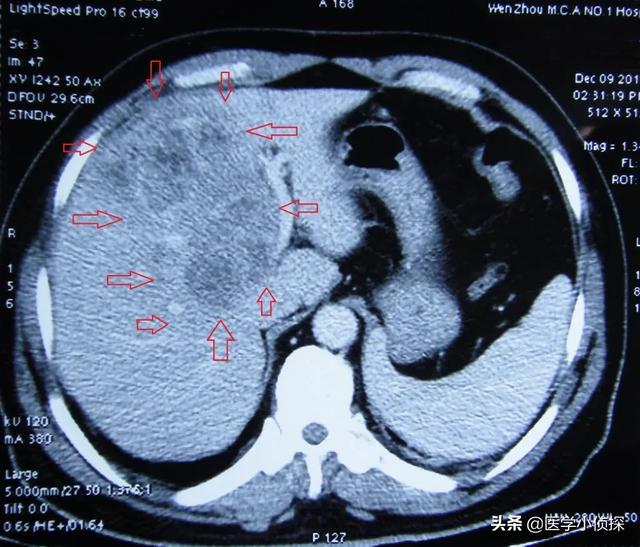

- まず、肝がんのスクリーニングには、超音波検査で1cm以上の肝腫瘍をはっきり検出できることと、肝がんの腫瘍マーカーであるα-フェトプロテインが肝がんの診断精度を強力に高めることから、超音波検査とα-フェトプロテインを組み合わせた検査をお勧めします。 この2つの検査の組み合わせは、精度も高く、費用も抑えられるので、費用対効果は非常に高いです。

- 肝臓の超音波検査で肝臓に腫瘍が見つからない場合、または腫瘍の性質が判断できない場合、αフェト蛋白の上昇は肝細胞癌の可能性を強く疑わせる。さらに肝臓のCTを行うこともある。強化CTは肝臓腫瘍の特定に比較的優れているので、すぐに肝臓の強化CTをお勧めします。

- スクリーニングの頻度について。肝がんの危険因子がない人は、年に1回検査を受けるだけでいいと思う。しかし、肝炎や肝硬変の既往がある人、肝臓がんの家族歴がある人、特に40歳以上の中高年には、年2回の検診をお勧めします。

- 肝臓の強化CTは肝臓癌の診断に一定の利点があるが、対応する放射線の存在により身体に一定の害をもたらすので、苦手な人は放射線の害がなく、肝臓の病変を明瞭に見ることができる肝臓の核磁気検査を受けることができる。